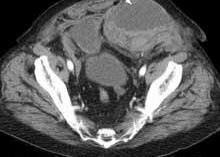

Psoas Avulsion Fracture

<div id="article-content-body"><p><img src="/sites/default/files/images/Con1PESporPAF.jpg" style="margin-right: 8px; margin-left: 8px; border: 1px solid black; float:...